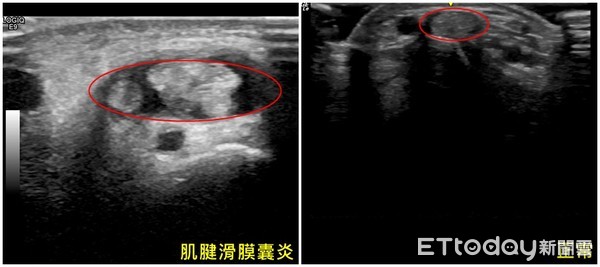

▲肌腱滑膜囊炎好發於50幾歲的健康婦女。(圖非當事人)

▲掃超音波檢查發現罹患媽媽手。(圖非當事人)